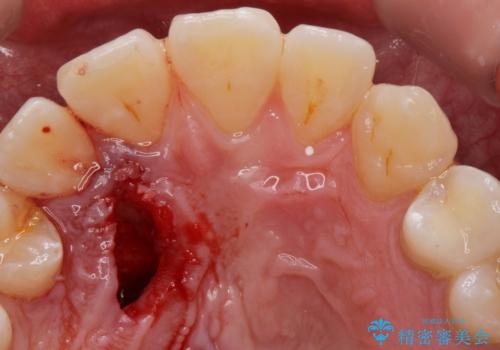

- 上顎の内側に歯が生えていて気になる。舌が当たって痛いとの事で来院。

レントゲンを確認したところ上顎の犬歯が歯列不正により内側から生えてきたものでした。

抜歯をして欲しいとの依頼でしたのでCTを確認しながら抜歯術を行いました。

無事に抜歯が終わりました。舌で触れても気にならなくなり満足して頂けました。